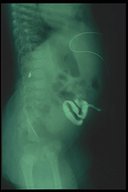

A catheter is introduce through the fistula for fistulogram

Plain X-ray showed that the catheter is located in the suprapubic region which is most likely in the bladder

Contrast study fills the bladder proving the fistula to be a patent urachus

Fistulogram demonstrates the tract connecting the umbilicus and the urinary bladder